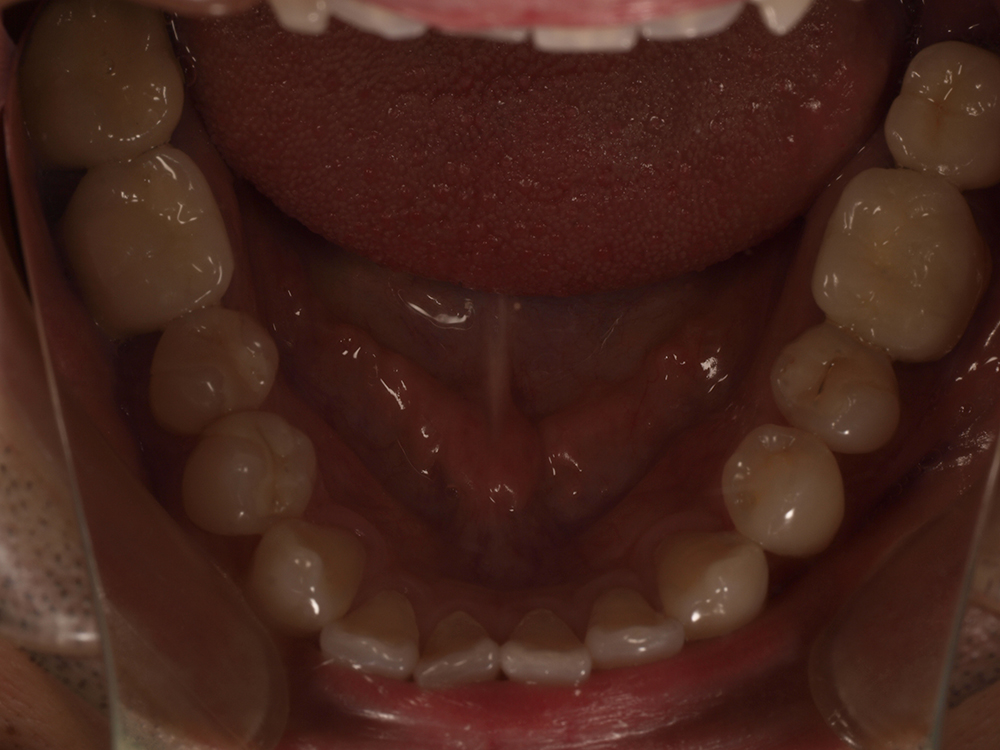

55歳 男性

- 主訴

- 前歯でしか咬めなく、食事を採るのに非常に困難で辛い

- 処置内容

- 上顎6本、下顎3本

- 治療費用

- 上顎:約230万(税込)下顎:約120万(税込)

- 治療期間

- 上顎:1年(仮歯まで8か月)下顎:8か月(仮歯まで5か月)

- リスク

- 上部構造物、仮歯の破折、術後の腫れ(3日)、人工歯根脱落リスクがあります